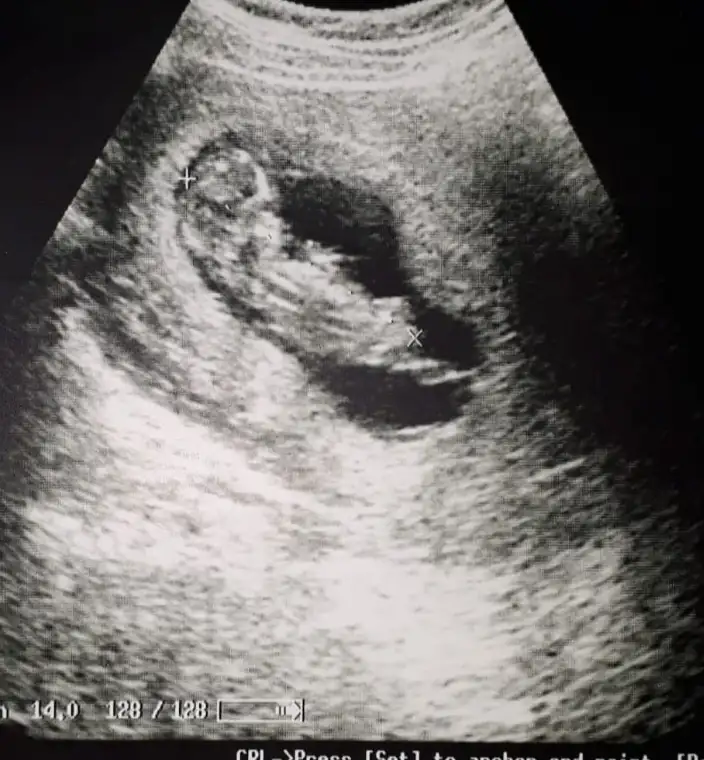

Slm cnm sağlıkla doğsun inşallah gönlündeki olsunSelam kızlar benim de 1 kızım var çok şükr yeni hamileyim ikincinin erkek olmasını çok istiyorum Rabbim gönlümüze göre versin![]()

Selam kızlar benim de 1 kızım var çok şükr yeni hamileyim ikincinin erkek olmasını çok istiyorum Rabbim gönlümüze göre versin![]()